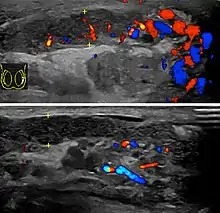

Epididimitis es un término médico que se refiere a una inflamación del epidídimo, la estructura tubular detrás del testículo donde maduran los espermatozoides y que conecta el testículo con los conductos deferentes.[1] Es un trastorno que resulta doloroso en varios grados y se suele acompañar con un enrojecimiento e hinchazón del escroto. La epididimitis es una de las causas más frecuentes de escroto agudo aunque rara vez puede ser una enfermedad crónica. Si el diagnóstico no se logra con la historia médica del paciente y su examen físico, un ultrasonido Doppler puede confirmar el aumento del flujo sanguíneo característico de un epidídimo inflamado.